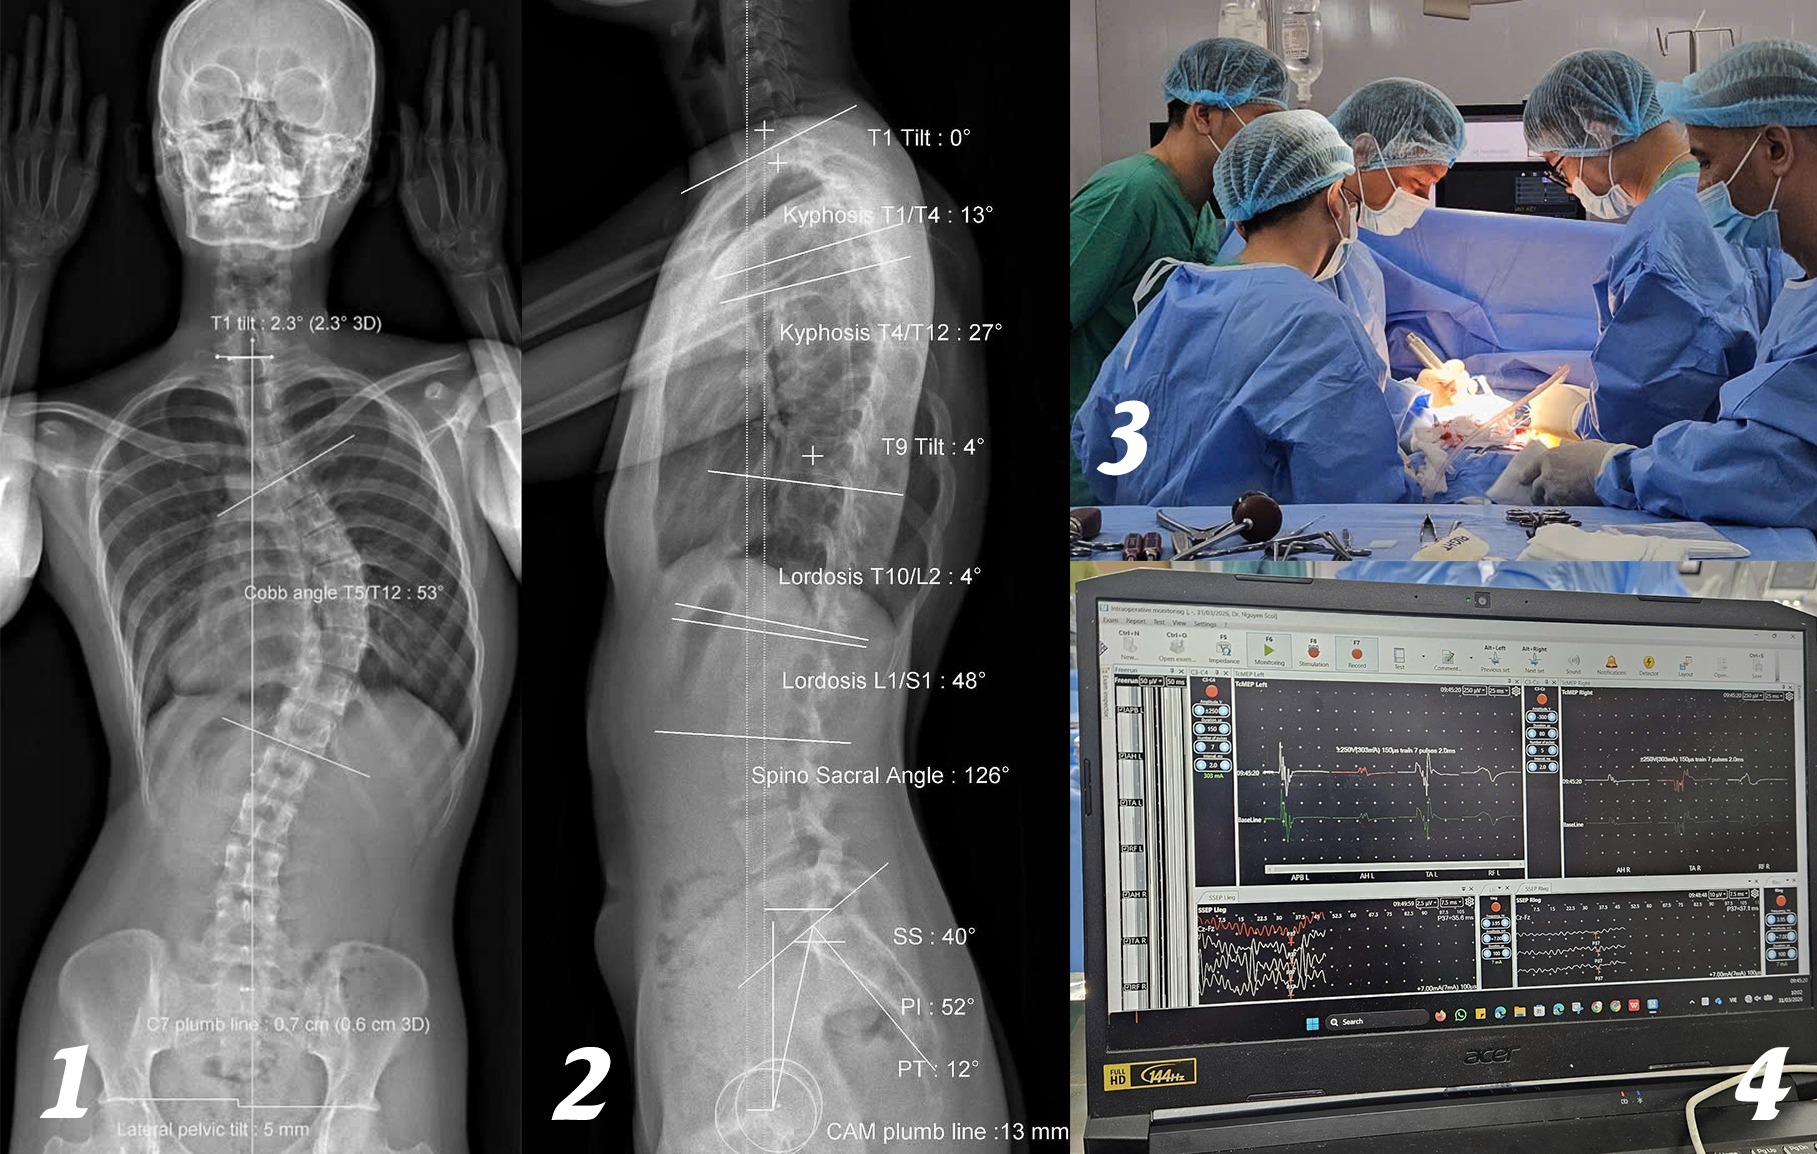

Điểm nổi bật của ca phẫu thuật này là việc ứng dụng hệ thống IOM (theo dõi điện sinh lý thần kinh trong mổ). Hệ thống này giúp giám sát liên tục tín hiệu thần kinh, kịp thời cảnh báo nguy cơ tổn thương tủy sống, biến chứng nặng có thể dẫn đến liệt. Nhờ đó, ê-kíp phẫu thuật có thể điều chỉnh thao tác ngay trong quá trình mổ, đảm bảo an toàn tối đa cho chức năng vận động của bệnh nhân.

Trong quá trình phẫu thuật, các bác sĩ đã tính toán kỹ lưỡng, nắn chỉnh các đốt sống bằng hệ thống vít ốc chuyên dụng để giúp cột sống của cô trở lại mức sinh lý nhất có thể. Sau 4 giờ, ca phẫu thuật thành công.